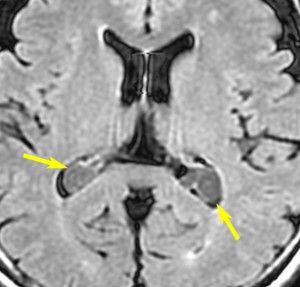

側頭部脈絡裂のう胞 temporal choroidal fissure cyst

内側側頭葉の側脳室側頭角の内側にできる小さなのう胞です。よくみるもので何もしないで放置します。通常は無症状ですが,とても大きくなると側頭葉てんかんを生じることがあります。組織は,choridal cyst, arachnoid cyst, glial cystなどと報告されています。

左側の画像は例外的に大きなものです。通常は10-20mmくらいの小さな丸いのう胞として見られます。